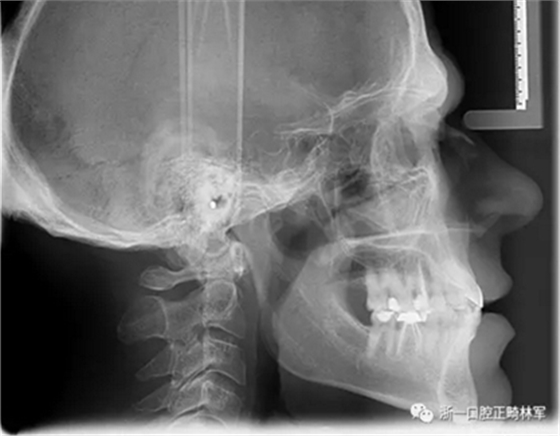

在最初的正畸咨询期间,拍摄了口内和口外照片连同一张全景片(图2),一张侧位头影片(图3)和正畸研究模型的海藻酸盐印模。

一位寻求改善微笑面容的43岁荷兰阿尔梅勒男子通过其全科牙医的介绍来到一家正畸医生的私人诊所,以纠正其错合畸形并在上颌前牙区域放置6个贴面。他属于牙形I类错合畸形,轻度骨性III类,覆合和覆盖减少以及前牙区存在间隙(图1)。